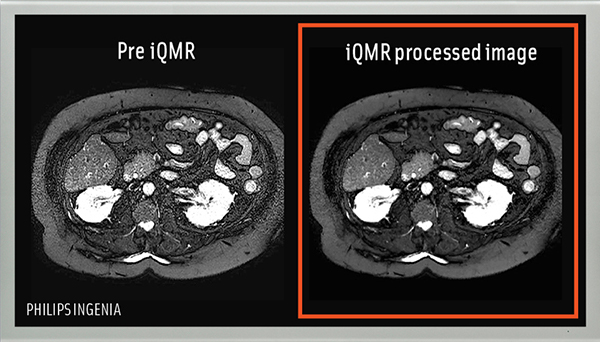

MRIによる画像診断は,検査に長時間を要するだけでなく,身動きが制限される・状況に応じて息を止めなければならない等,患者に負荷のかかる検査を要する点が課題として挙げられている。「iQMR」は統計的手法を用いてMRI画像のノイズを低減するソフトウェアで,医療施設などで使用中のMRI機器に接続するだけで機能を追加できるシステム。MRIは通常,撮影時間が短くなるほどノイズが発生して診断が難しくなるが,「iQMR」を導入すると,従来の画像レベルを維持したまま撮影時間を平均で3割短縮でき,患者および医療従事者の負荷軽減につながることが期待される。

MRI撮影画像

iQMR導入前 iQMR導入後